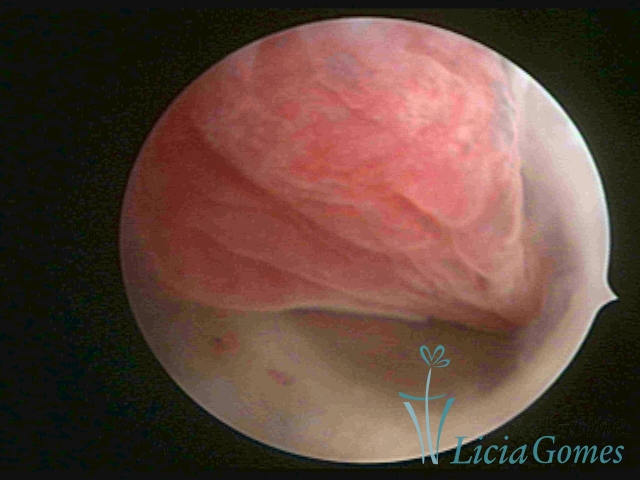

ENDOCERVICAL POLYPS

Benign tumors resulting from the reactive focal proliferation to inflammatory processes or hyperestrogenism situations, which may be sessile (with a large implantation) or stalked.